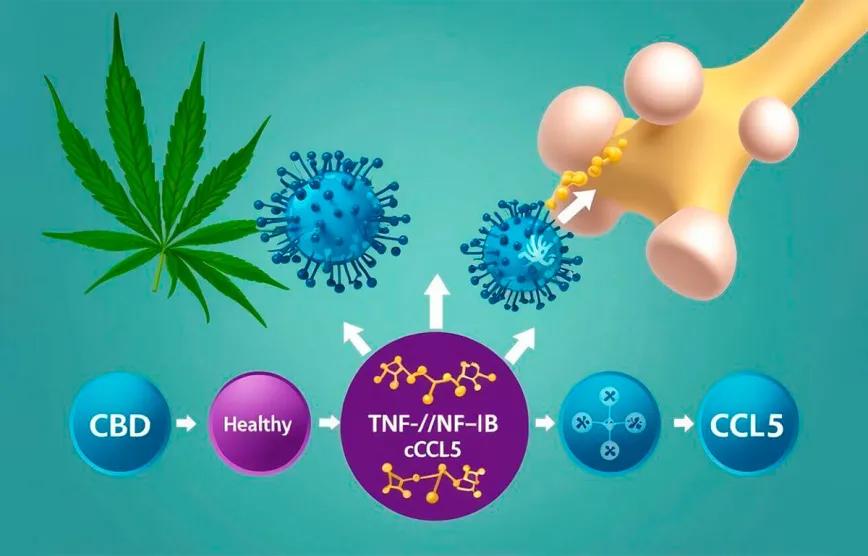

El estudio empleó modelos celulares y animales para evaluar los efectos del cannabidiol sobre la proliferación, migración e invasión de células de osteosarcoma. Los resultados fueron contundentes: el CBD redujo significativamente la viabilidad de las células cancerígenas sin afectar a las células óseas sanas, y atenuó el crecimiento tumoral en ratones. A nivel molecular, los investigadores identificaron que el CBD se une directamente a la subunidad p65 del factor de transcripción NF-κB, interfiriendo con su capacidad para activar la expresión del quimioatrayente CCL5, una proteína implicada en la inflamación tumoral.

Este hallazgo resulta especialmente relevante porque el eje TNF-α/NF-κB/CCL5 se ha vinculado con la progresión de diversos tipos de cáncer. En el caso del osteosarcoma, el estudio demostró que existe un bucle de retroalimentación positiva entre p65 y CCL5 que perpetúa la señal inflamatoria y estimula el crecimiento tumoral. El cannabidiol interrumpe este ciclo, debilitando tanto la inflamación como la proliferación de las células malignas.